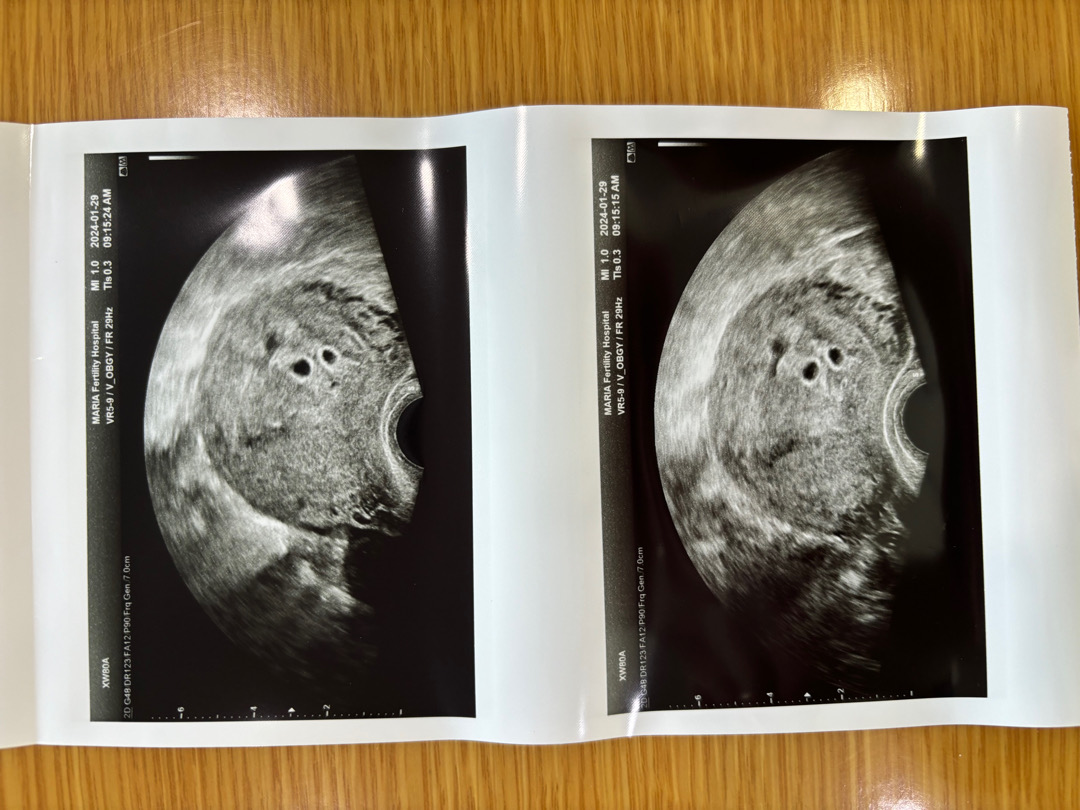

설마설마했는데 둥이래요+_+ㅎㅎ 놀란하루 복잡한 생각 감사한생각 여러가지감정이드는 하루입니다. 5주차 2번째피검 5858 수치라네요ㅎ